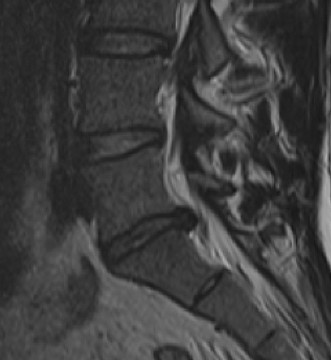

Prognosis of central cord syndrome? Indications for surgery for this disorder? CASE 2 A 56-year-old man presents to you with a chief complaint of severe right buttock, posterior thigh, and lower leg pain for 12 weeks. It radiates to the lateral aspect of his foot, and it is worse with sitting or standing for prolonged periods and with walking. Now over the past 2 weeks, he reports difficulty with toe push-off on the right side. Treatment so far has been nonsteroidal anti-inflammatory drugs (NSAID), physical therapy, and an epidural injection without significant relief. Physical examination findings include 4/5 right ankle plantar flexion, a positive straight leg raise on the right, and an absent right Achilles tendon reflex. Images of his lumbar spine are shown in Figures 1–4 and 1–5.

Figure 1–5

The correct answer is (C). The patient presents with classic right S1 radiculopathy and new onset plantar flexion weakness. The images demonstrate a right-sided paracentral disc herniation at L5/S1 compressing the traversing S1 nerve root. Despite nonoperative management, he continues to have severe pain and new weakness. Continued physical therapy or an epidural injection is unlikely to improve the patient’s pain at this time. In the setting of neurological decline, surgery is more strongly indicated. Lumbar discectomy is the most appropriate procedure for this patient. Fusion would only be indicated if there were radiographic signs of instability, which are not present.